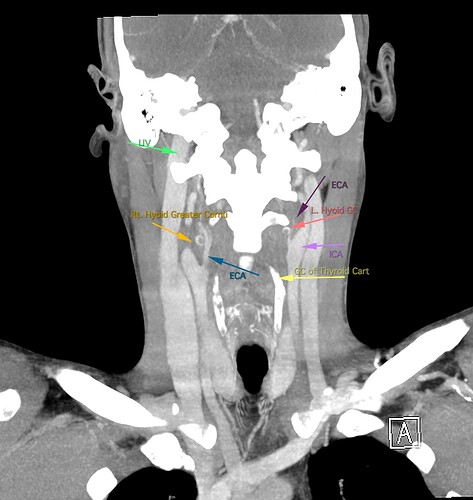

So, 2 years ago was the first time I came across Living with Eagle, filled with descriptions of all my symptoms, and a slew of scans showing very obvious bone chunks in the neck. Since I studied bio in college, and these bones are obvious, I figured I’d take a stab at looking at my own past scans and, low and behold, mild–but present–ossification of my stylohyoid ligament. Perhaps more relevant in my case, in the process of learning enough of the anatomy to understand axial images I noticed another weird thing–my right external carotid artery is in the wrong place. Instead of sitting lateral to my hyoid greater cornu, it’s medial. Hmm.

Tonsil surgery did solve the problem of my tonsils hurting, because they were gone, but no resolution of other symptoms. This was a year ago. I’ve been to PT, SLP, and now back to PT while I trial gabapentin for the neurologist. PT#2 discovered a bunch of significant atrophy in my upper right shoulder/back, and, you guessed it it’s all right sided. I’ve since then, thanks to radiopedia and Netter’s, also explored my images and noticed a few other anomalies in my scans, including an extended right thyroid superior cornu which appears to be pressing strongly into my neck also in the general area of pain, and an occipital artery branching off and wrapping around the internal carotid. Frustratingly these also weren’t mentioned on rads reports. My swallow study by the SLP showed obvious asymmetry with my swallow, but the SLP reported it symmetric and radiology apparently doesnt read the A/P view in their modified barium swallow studies? This is not inspiring faith in the academic institution I attended, but what can I possibly know they dont?